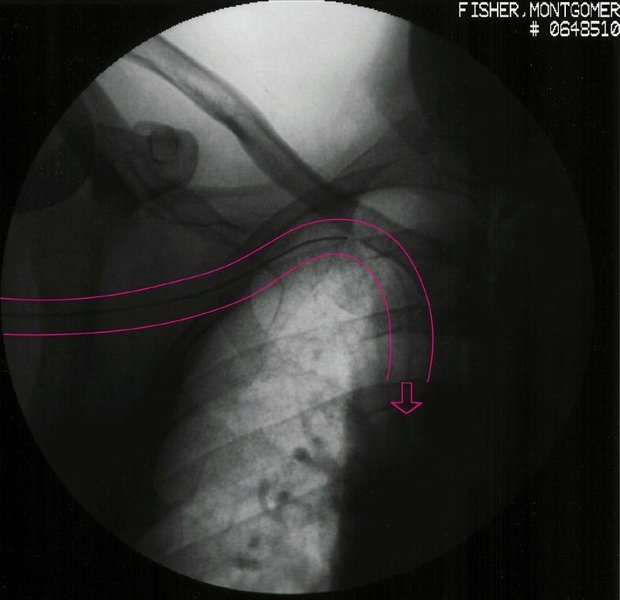

Monte's PICC line